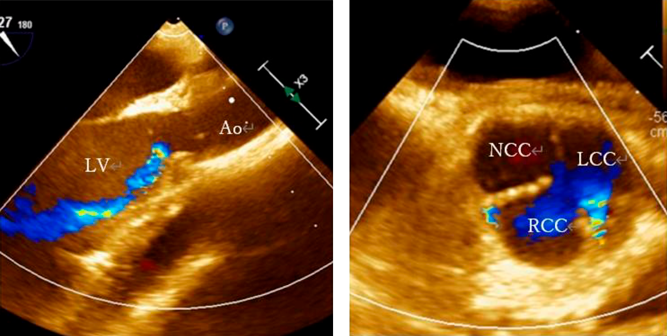

A 12-year-old girl with an anomalous origin of the left coronary artery from the right coronary cusp, characterized by intramural course of the coronary artery, underwent unroofing of the left main trunk. During the surgical procedure, aortic regurgitation (AR) emerged, prompting us to attempt commissural suspension and plasty to the right coronary cusp. Despite the aortic valve intervention included within a total cardiac arrest duration of 174 minutes, a trivial-mild degree of AR persisted. Subsequently, AR through the central and commissural regions between the left and the right coronary cusps progressively deteriorated (Fig. 1). The left ventricular end-diastolic diameter increased from 42 mm to 45 mm over a period of six months. Cardiac catheterization performed three months postoperatively revealed left ventricular end-diastolic pressure of 16 mmHg, AR being categorized as Sellers IV. Despite the absence of a discernible pressure gradient, morphological constriction was noted at the sino-tubular junction (Fig. 2A). Additionally, contrast-enhanced computed tomography confirmed the narrowing of the sino-tubular junction (Fig. 2B). Given the patient’s age and activity level, we considered AVNeo as a viable alternative to mechanical valve replacement.

Fig. 1 Preoperative images on trans-esophageal echocardiography

Ao, aorta; LV, left ventricle; LCC, left coronary cusp; NCC, non-coronary cusp; RCC, right coronary cusp